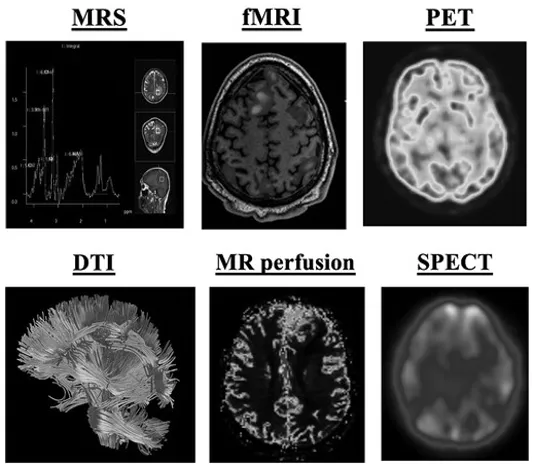

低级别胶质瘤是中枢神经系统内胶质细胞癌性生长的亚型,其特点是生长缓慢且恶性程度相对较低。尽管其侵袭性较低,但这些肿瘤仍可通过压迫周围神经和血管结构而引起显著的神经系统症状...